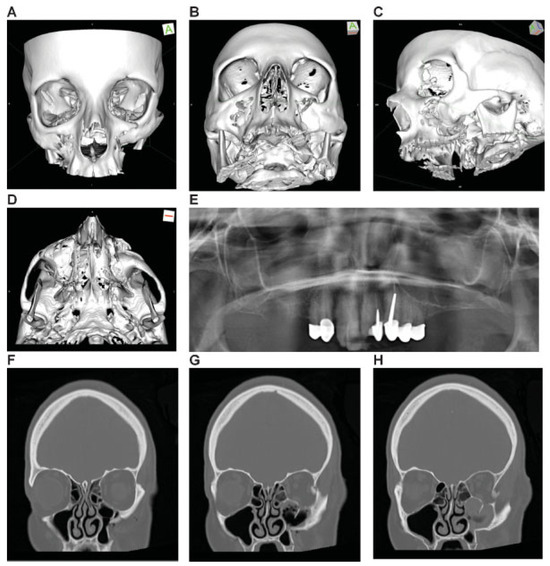

Figure 10.

Lateral cranio-orbito-facial Injury: fronto-spheno-zygomatico-orbital fracture. Imaging: Three-dimensional (3D) computed tomographic scans (A) frontal view, (B) lateral view left, and (C) oblique lateral view right. Narrative description: Large-sized fragment of left frontotemporal vault and skull base including all four orbital walls. Displaced (caudolateral) monofragment of left zygoma in continuity with infraorbital rim and antral wall, leading to an extreme diastasis of left lateral orbital wall, multifragmentation along the posterior articulations of the zygoma and in the frontotemporal transition (greater wing of sphenoid). (D) Level 3 Code: 92 m.Omil.I1i.Z1li - 93 m.Oas.M0.A0.S1 - 94 m.F1m, Orbit (left): R(slim).W1(slim)2(slim).A(slm). This case example CMTR-92-106 is made available electronically for viewing using the AOCOIAC software at www.aocmf.org/classification.

Figure 11.

Panfacial fracture including lower central midface fracture analogous to Hemi Le Fort I fracture. Imaging: Three-dimensional (3D) computed tomographic (CT) scans—(A) frontal view, (B) oblique lateral view right, (C) oblique lateral view left, (D, E) coronal CT scans; (F, G) axial CT scans; (H, I) sagittal CT scans; 3D CT scan details—(J) superofrontal view, (K) palatal from below, (l) pterygomaxillary junction. Narrative description: Midface component of panfacial fracture: LCM fracture left, paramedian midline fracture of the palate; left maxillary alveolar process fracture 11–13, vertical tooth fracture 14, avulsion 15. Details: Dentition (FDI) preinjury: completely dentate. Palate: Paramedian fracture left. Pterygoids: No involvement. Displacement: Anterosuperior displacement of the LCM fragment left, multifragmentation of the antral wall left, Infraorbital rim left intact. Internal orbits: No involvement. (M) Level 3 Code : 91 P.A.S.P - 92 La.P2.L1. This case example CMTR-92-103 is made available electronically for viewing using the AOCOIAC software at www.aocmf.org/classification. Mandible component according to level 2: four fracture regions: condylar process bilaterally, right angle/ramus and symphyseal region. Mandible component according to level 2: four fracture regions: condylar process bilaterally, right angle/ramus and symphyseal region.